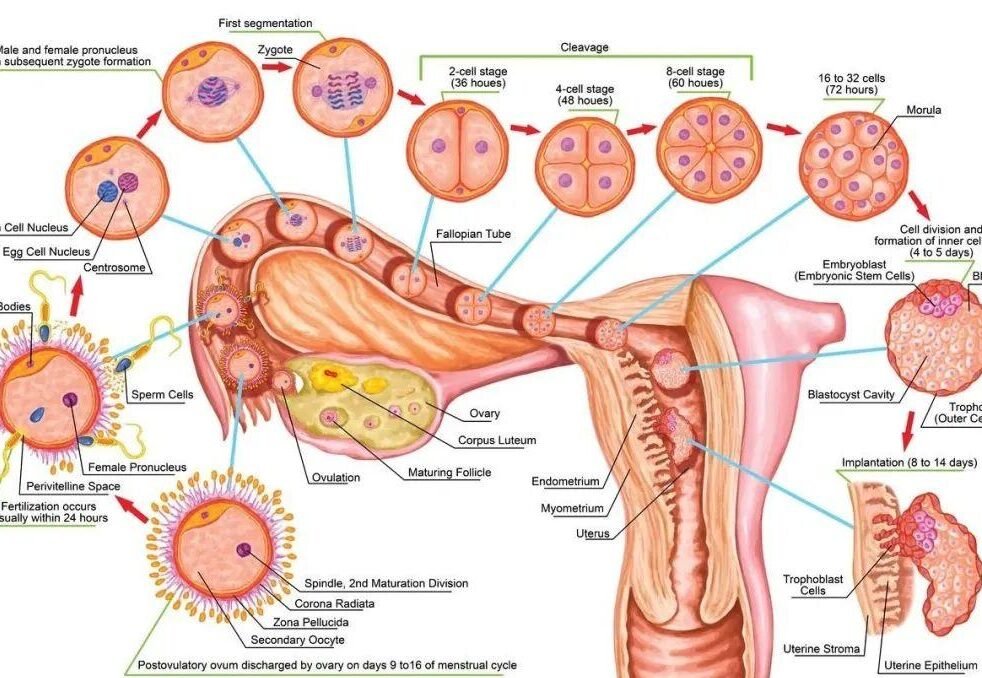

Precise quantification of embryo type: cumulative transfer of ≥4 AA blastocysts or ≥10 zygotic stage embryos that failed to implant (ESHRE Consensus 2025)

New indicator for time dimension: ≥3 transfer failures with fluctuating intima-media thickness of <0.5mm within 2 years (suggestive of tolerance injury)

II. Three-dimensional breakthrough strategies for embryo quality

1. Iterative Revolution in Chromosome Screening

PGT-A Plus technology:

▶ Simultaneous detection of monogenic disease + chromosomal aneuploidy + mitochondrial copy number (mtDNA)

III. Molecular-level repair of endometrial tolerance

1. Precise diagnosis of “soil deprivation